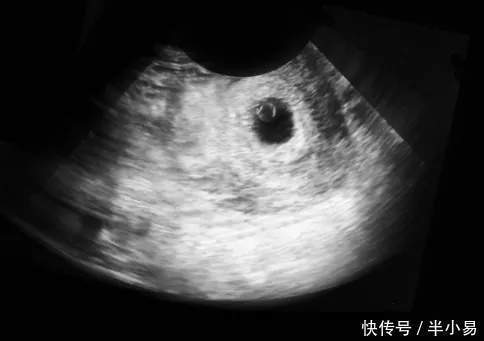

怀孕22天胎宝宝在你肚子里也就小黄米那么大,不过你放心即使这么点的小胎儿也已经在你身体里安营扎寨了,用专业一点的话说已经开始在子宫“着床”了。

别看它只有小黄米那么大,但它的细胞和组织都有在按照指令有条不紊地快速生长中。不要急不要躁,你将会在258天左右看到一个可爱迷人的胎宝宝。

最后我们再来总结一下:怀孕22天胎宝宝正在努力地发育生长,只有小黄米那么大;部分准妈妈已经开始出现早孕反应了。别担心一切都是正常现象,恭喜你你即将迈入一个丰富多彩的孕期生活。